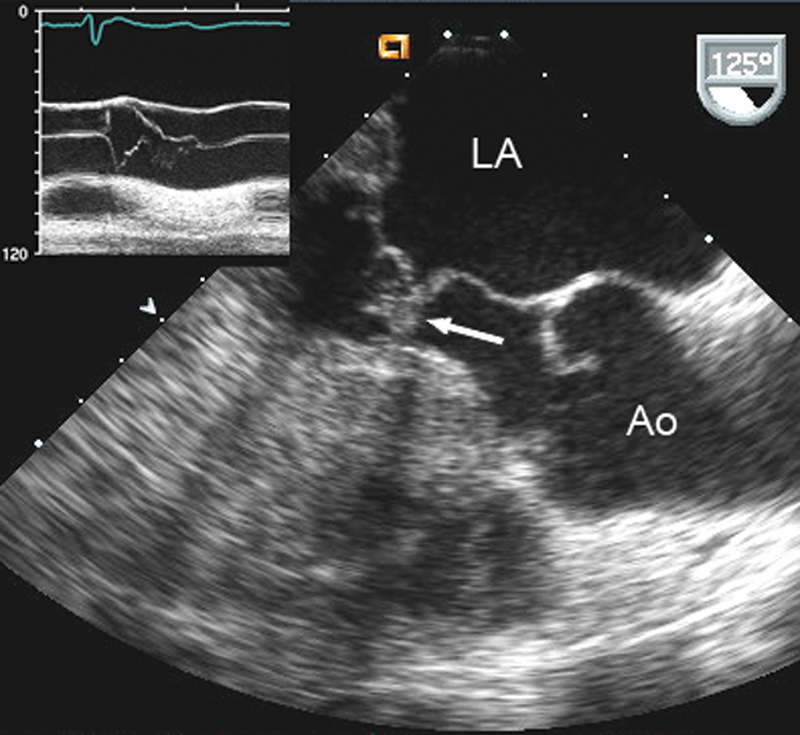

فحوصات تشخيصية لبعض امراض القلب والشرايين التاجية